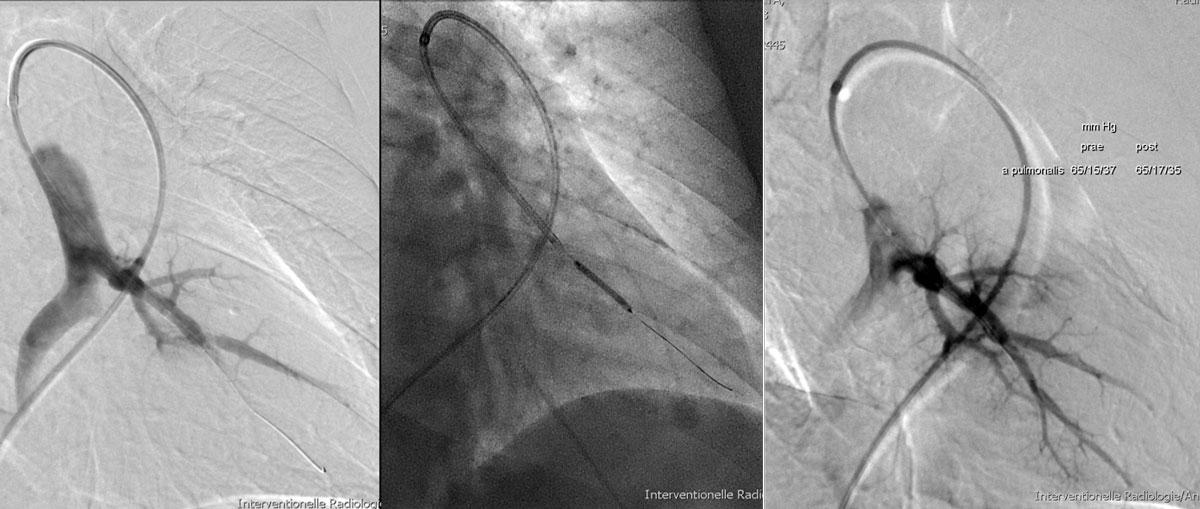

Since 2001, reports have emerged, mainly from Japan, of innovative BPA for mainly females not eligible for surgery owing to comorbidities [105–108]. Multiple angioplasty procedures in single patients were necessary to achieve a significant reduction of the PVR and the studies were not randomised-controlled. However, haemodynamic improvements reported were impressive and so were improvements in the 6-minute walk distance and NYHA/WHO functional class. In general, lobar and proximal segmental disease is better suited for surgical resection, whereas distal segmental and subsegmental disease is more appropriate for BPA [109] (fig. 17).

Figure 17 Balloon pulmonary angioplasty angiography demonstrating a well-perfused segment of a left sided pulmonary artery segment after dilatation. (Courtesy of Prof. T. Pfammatter.)

Many questions remain unresolved about this new intervention, such as patient selection, risk of bleeding, vessel rupture, restenosis rate and other complications [109]. Data on long-term results are not yet available [109].

In recent series, BPA periprocedural mortality ranged from 0 to 10% [106–108, 110–114]. The two most common complications of BPA were reperfusion pulmonary oedema and pulmonary vascular injury, with rare episodes of vessel perforation or rupture [109]. Despite the advances in and improvement of the procedure, reperfusion pulmonary oedema remains a frequent complication of BPA with an incidence as high as 53 to 60% in some studies [107, 108]. Pulmonary artery perforation or rupture is a serious complication of BPA and is reported in 0 to 7% of procedures [109]. Thus, this treatment modality should be reserved for expert centres offering rescue and salvage strategies [109]. As pointed out in the previous paragraphs, the concentration of BPA also to expert centres is mandatory and again should be limited to no more than one or two centres in Switzerland.